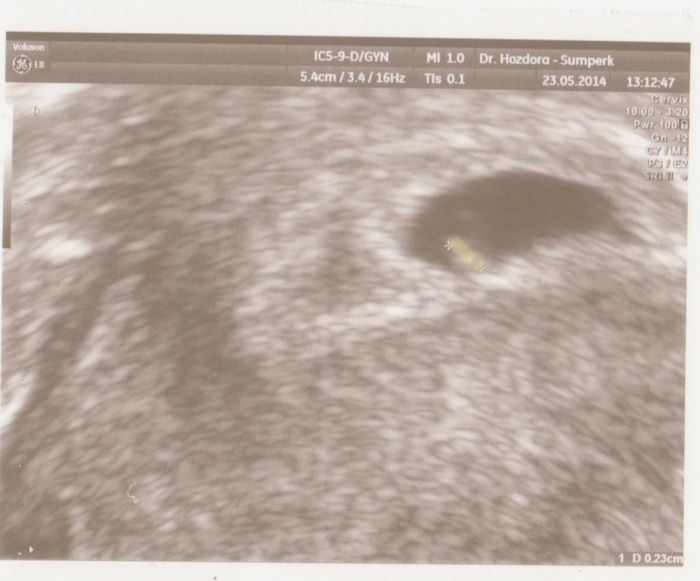

Děvčata,obě srdečně zdravím....děkuji oběma za gratulace. Upřímně,moc se mi nechtělo dávat sem obrázky mimíska,dokud se vám to nepovede taky,připadalo mi to takové blbé.tak po naléhání vyhovuji všim přáním a zde přikládám dvě fotky z ultrazvuků